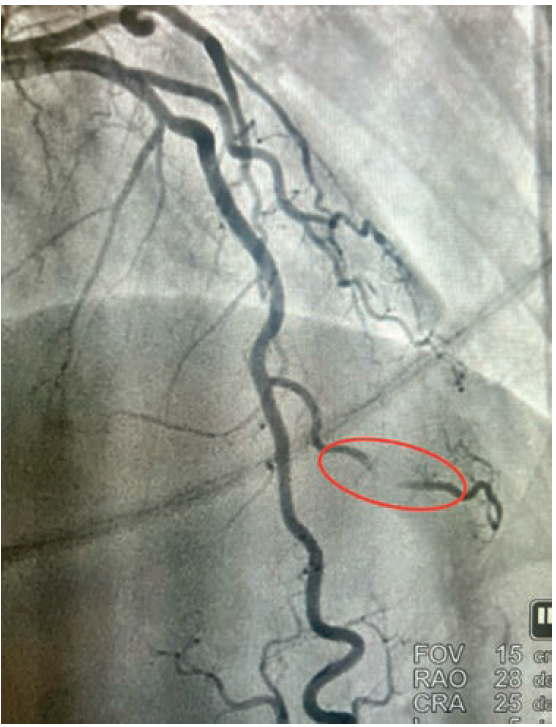

Myocardial “Milking” in a Diagonal Branch Artery

Read the case "Rare Case of Myocardial “Milking” in a Diagonal Branch Artery (Expanded)" by Richard Casazza, MAS, RT(R)(CI); Arsalan Hashimi, MD; Nicole DeLeon, MD; Enrico Montagna, RT(R)(CI); David J. Epstein, MD